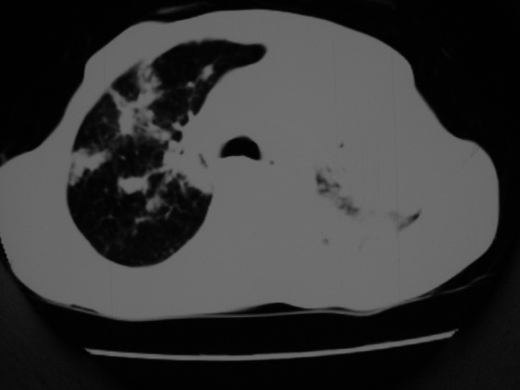

男69岁,年前胸片示肺感染治疗近一月今复查无明显好转,血象正常

双肺内不规则斑点状 片状及结节密实影,部分灶周见索条样影及\"树芽征\",左肺上叶实变,内见充气支气管影及斑状钙化,左侧少量胸腔积液,考虑1)双肺结核2)左侧胸腔积液

右肺多发片絮状结节状及时条索状影,左上肺实变,内可见虫蚀样空洞及支气管气象,左下肺片状及球形病灶,及胸腔积液征象,双肺病灶内多发钙化影,结合病史,考虑双肺继发型肺结核,左胸腔积液

右肺多发片絮状结节状及时条索状影,左上肺实变,内可见虫蚀样空洞及支气管气象,左下肺片状及球形病灶,及胸腔积液征象,双肺病灶内多发钙化影,上纵隔向左侧移位,结合病史,考虑双肺继发型肺结核,左胸腔积液。

右肺多发片絮状、结节状及条索状影,左上肺实变,内可见虫蚀样空洞及支气管气象,左下肺片状及球形病灶,有胸腔积液征象,双肺病灶内多发钙化影,上纵隔向左侧移位,结合病史,考虑双肺继发型肺结核,左胸腔积液。 建议结合ppd检查或纤支镜检查!